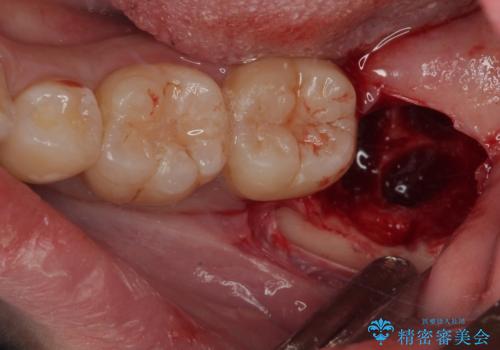

CTで神経の位置などを確認し、抜歯術を行いました。

一週間後に抜糸を行いました。

しっかり麻酔が効いたことを確認してから安全に抜歯を行いました。